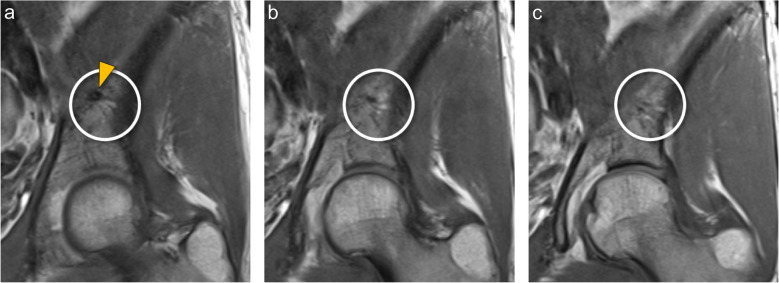

Materials and methods: MRI-examinations of the pelvis in 245 patients were analyzed retrospectively. Prominent nutrient vessels of the ilium were recorded, including vessel origin, anatomical characteristics such as branches, bone-marrow changes, and entry points into the bone.

Results: Two hundred forty-five patients (54±16 years, range 18-88, 102 males) were included. Prominent central nutrient vessels were found in virtually all patients on both sides of the ilium. All nutrient vessels arose from the iliolumbar artery, forming a breakthrough-anastomosis to the superior gluteal artery. Two branches were seen in 57.6% on the right and 61.2% on the left side, constituting the most prevalent branching pattern. Three branches were seen in a third for each side. One or four branches were seen in 3-4.5% for both sides. A prominent branching pattern we coined "central-vessel-convolute" (CVC) at the central part of the ilium was seen in 75% on either side. Perivascular fatty areas were found in 25% of cases, and in 3.7-2.4% adjacent bone-marrow edema was observed.

Conclusion: Prominent nutrient vessels in the ilium are seen in almost all individuals, the majority exhibiting a specific CVC-pattern. These vessels may be surrounded by perivascular fatty areas; adjacent bone-marrow edema is rare. Recognizing the CVCs and the associated imaging findings should facilitate distinguishing normal anatomical structures from pathology.